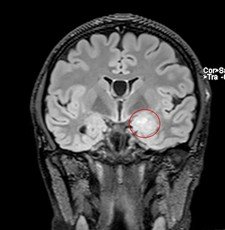

Pentru pacienți, aceste episoade sunt adesea greu de înțeles și pot fi însoțite de teamă și incertitudine. Investigațiile imagistice au adus însă explicația: RMN-ul cerebral a evidențiat o mică tumoră profundă, situată pe fața internă a lobului temporal stâng, la nivelul hipocampului și al nucleului amigdalian.

Deși tumora era relativ mică – aproximativ doi centimetri – localizarea ei era extrem de delicată. Hipocampul este una dintre structurile centrale ale creierului, implicată în memorie și procesarea emoțiilor, iar lobul temporal stâng joacă un rol important în limbaj.